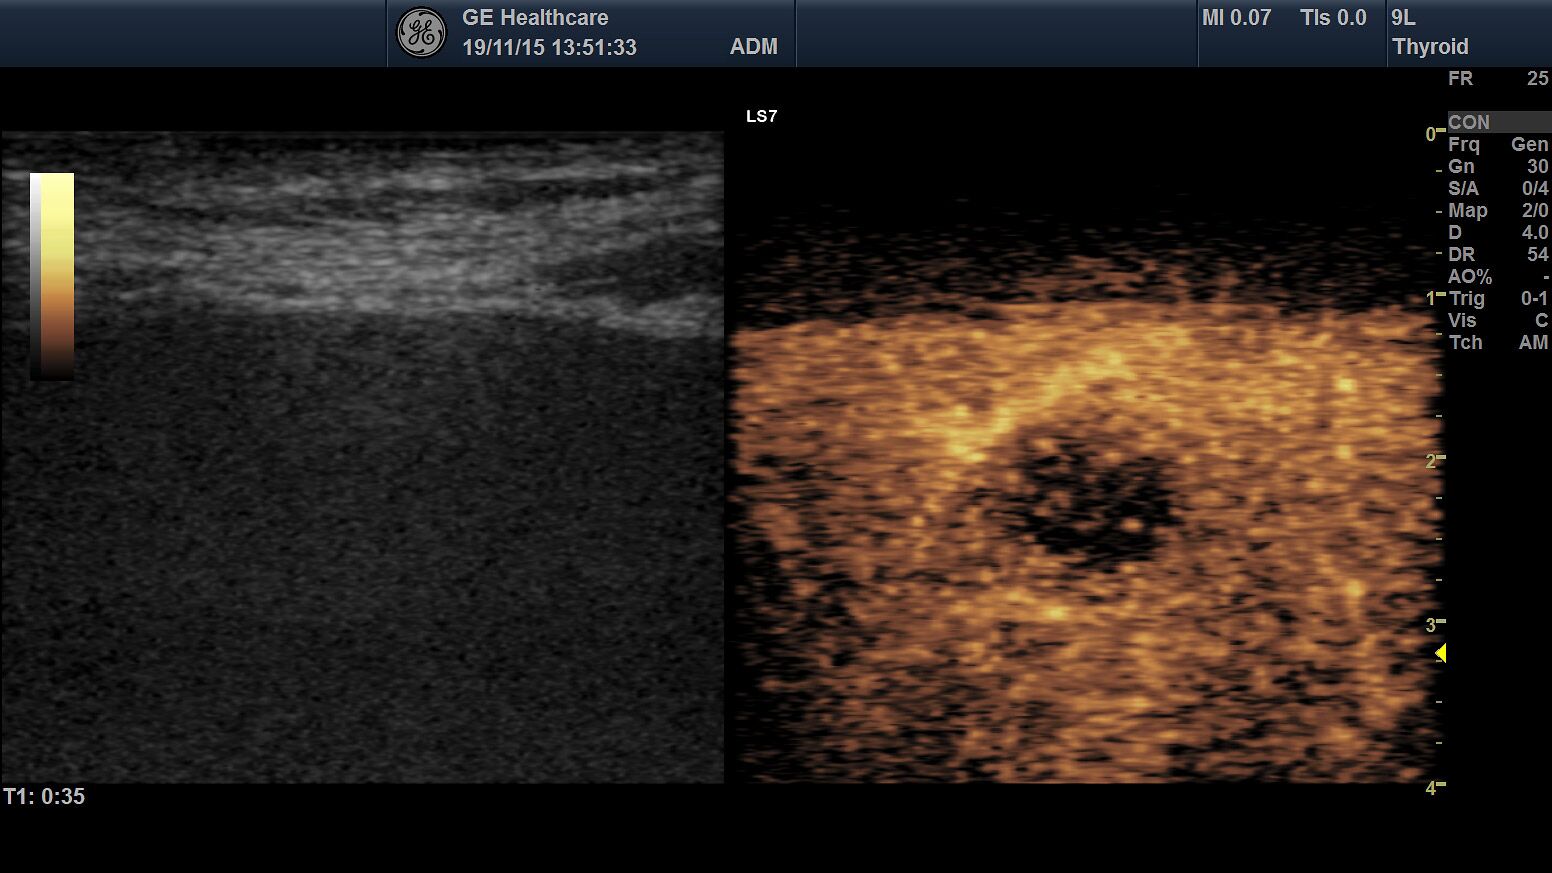

Die Ultraschall-Untersuchung ist mit Recht eine der wichtigsten und häufigsten Untersuchungsmethoden. Der Ultraschall ist ein bildgebendes Verfahren. Er erlaubt, von außen in den menschlichen Körper hinein zu sehen. So können die inneren Organe enorm detailreich und aussagekräftig untersucht werden. Vor allem die Weichteile wie Leber, Bauchspeicheldrüse, Galle, Niere oder Milz, die beim Röntgen nur schlecht zu sehen sind, können ausgezeichnet dargestellt werden.

Die Ultraschalluntersuchung ist ein sehr schnelles und leistungsstarkes Diagnoseverfahren. Dabei kann der Arzt Abläufe im Körper in Echtzeit sehen! Er hat keine Momentaufnahme vor sich, wie auf den Bildern des Röntgens oder der Computertomographie, sondern ein bewegtes Bild. Um zum Beispiel die Darmbeweglichkeit oder Organdurchblutung darzustellen, ein großer Vorteil. Da Sie als Patient dabei nicht in einer Röhre liegen, sondern ihr behandelnder Arzt neben Ihnen ist, kann ganz gezielt untersucht werden; dabei Beschwerdepunkte gezeigt, Befunde direkt erläutert und das weitere Vorgehen abgesprochen werden.